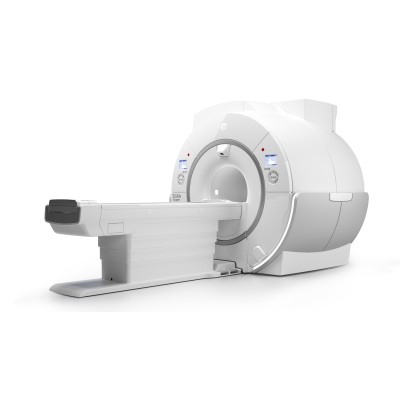

SIGNA Voyager поможет вам значительно увеличить рентабельность вложенных средств. Поскольку SIGNA Voyager — одна из самых малогабаритных среди аналогичных систем с широкой апертурой 1.5Т, что значительно сокращает затраты на инсталляцию. А благодаря низкому уровню энергопотребления ваши эксплуатационные расходы снизятся до минимальных значений.

SIGNA Voyager поможет вам значительно увеличить рентабельность вложенных средств. Поскольку SIGNA Voyager — одна из самых малогабаритных среди аналогичных систем с широкой апертурой 1.5Т, что значительно сокращает затраты на инсталляцию. А благодаря низкому уровню энергопотребления ваши эксплуатационные расходы снизятся до минимальных значений.

| Основные характеристики | |

| Производитель | GE |

| Класс оборудования | Экспертный |

| Мощность | 1,5Т |